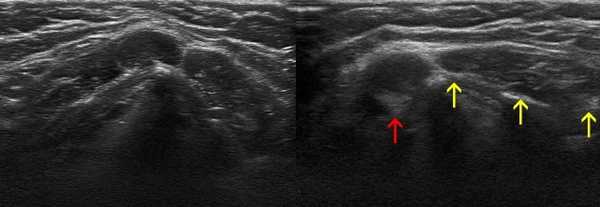

Ультразвуковое исследование лимфатических узлов шеи

УЗ-сканирование при поражении подчелюстных ЛУ обычно проводят в комплексе с визуализацией мягких тканей лица и шеи.

Осложнения при заболеваниях ЛОР-органов влияют на особенности УЗ-визуализации лимфоузлов шеи - последние на экране ультразвукового сканера могут выглядеть как анэхогенные жидкостные образования либо как участки низкой и высокой эхогенности, чередующиеся друг с другом. Указанные изменения на снимках характерны для гнойного расплавления и формирования аденофлегмоны.